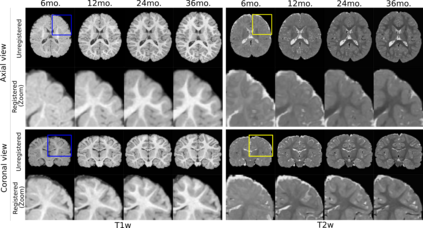

Recent self-supervised advances in medical computer vision exploit global and local anatomical self-similarity for pretraining prior to downstream tasks such as segmentation. However, current methods assume i.i.d. image acquisition, which is invalid in clinical study designs where follow-up longitudinal scans track subject-specific temporal changes. Further, existing self-supervised methods for medically-relevant image-to-image architectures exploit only spatial or temporal self-similarity and only do so via a loss applied at a single image-scale, with naive multi-scale spatiotemporal extensions collapsing to degenerate solutions. To these ends, this paper makes two contributions: (1) It presents a local and multi-scale spatiotemporal representation learning method for image-to-image architectures trained on longitudinal images. It exploits the spatiotemporal self-similarity of learned multi-scale intra-subject features for pretraining and develops several feature-wise regularizations that avoid collapsed identity representations; (2) During finetuning, it proposes a surprisingly simple self-supervised segmentation consistency regularization to exploit intra-subject correlation. Benchmarked in the one-shot segmentation setting, the proposed framework outperforms both well-tuned randomly-initialized baselines and current self-supervised techniques designed for both i.i.d. and longitudinal datasets. These improvements are demonstrated across both longitudinal neurodegenerative adult MRI and developing infant brain MRI and yield both higher performance and longitudinal consistency.